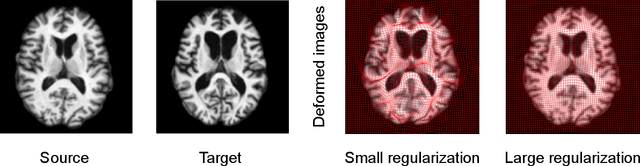

This paper presents a predictive model for estimating regularization parameters of diffeomorphic image registration. We introduce a novel framework that automatically determines the parameters controlling the smoothness of diffeomorphic transformations. Our method significantly reduces the effort of parameter tuning, which is time and labor-consuming. To achieve the goal, we develop a predictive model based on deep convolutional neural networks (CNN) that learns the mapping between pairwise images and the regularization parameter of image registration. In contrast to previous methods that estimate such parameters in a high-dimensional image space, our model is built in an efficient bandlimited space with much lower dimensions. We demonstrate the effectiveness of our model on both 2D synthetic data and 3D real brain images. Experimental results show that our model not only predicts appropriate regularization parameters for image registration, but also improving the network training in terms of time and memory efficiency.